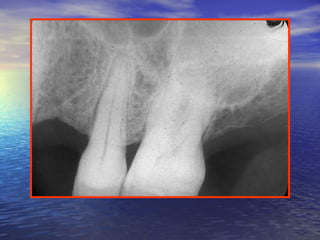

The extension of sinus floor into theThe extension of sinus floor into the

alveolar process may make this floor to bealveolar process may make this floor to be

found between the root of adjacent teeth asfound between the root of adjacent teeth as

well as the roots of all individual tooth.well as the roots of all individual tooth.

The apices may become protruded into theThe apices may become protruded into the

sinus cavity and are covered by asinus cavity and are covered by a

combination of the PDL and mucouscombination of the PDL and mucous

membrane that lines the sinus.membrane that lines the sinus.

Relationship of the floor of the sinus to the roots of theRelationship of the floor of the sinus to the roots of the

maxillary teethmaxillary teeth

Enlargement of the sinus toward theEnlargement of the sinus toward the

alveolar process may place the floor of thealveolar process may place the floor of the

sinus in a position :sinus in a position :

lower than that of the floor of the nasallower than that of the floor of the nasal

cavity .cavity .